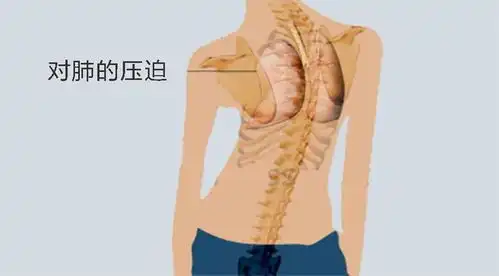

脊柱侧弯注意睡姿能矫正侧弯吗

万万没想到这种睡姿会导致脊柱侧弯

脊柱侧弯最全的康复训练方案

一女生睡姿不对致脊柱侧弯睡觉究竟侧卧好,还是平躺好

脊柱侧弯纠正大法多图详解,赶紧转走

体检发现脊柱有侧弯,该如何改善